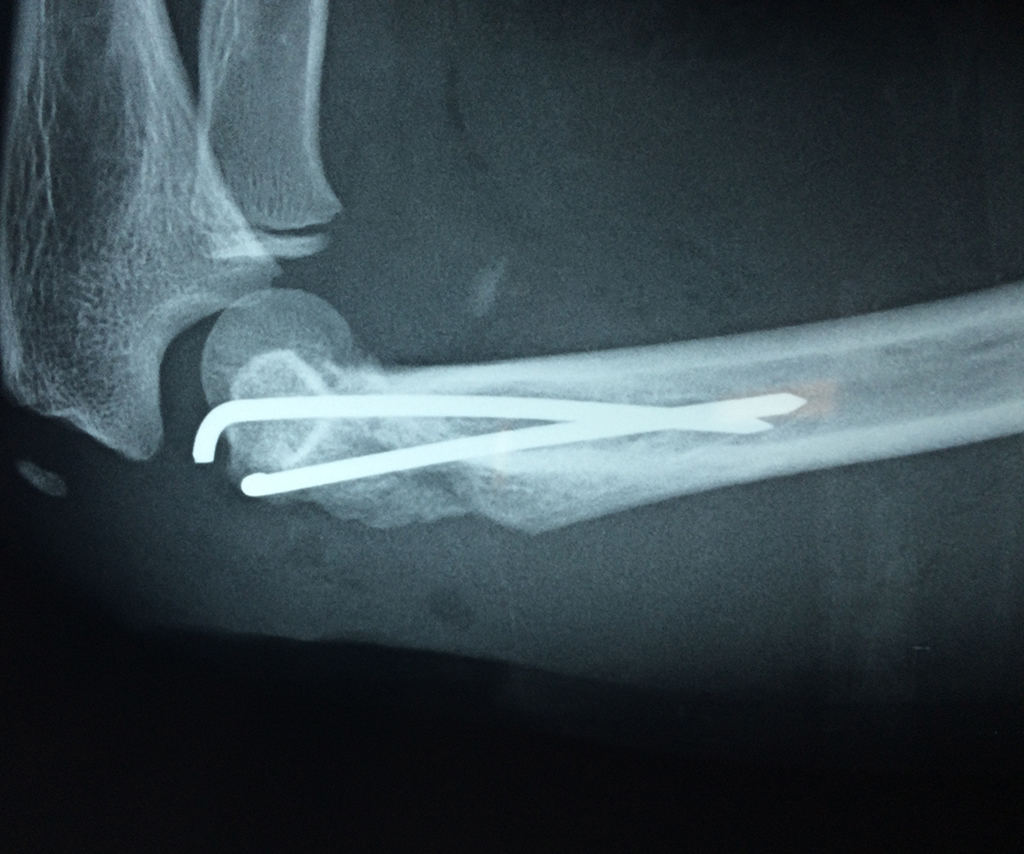

En anatomía humana, la articulación del codo es la que une el brazo con el antebrazo, conectando la parte distal del hueso húmero con los extremos proximales de los huesos cúbito y radio.

La articulación principal que constituye el codo se denomina humero radio-cubital y puede dividirse en dos partes bien diferenciadas, la articulación humero-radial y la humero-cubital.

Por otra parte el cúbito y el radio forman también una articulación entre si en las proximidades del codo, la cual se denomina articulación radio-cubital proximal.

Los extremos óseos se conectan entre si por un conjunto de ligamentos que contribuyen a su fijación y están rodeado por una estructura común que se llama cápsula articular, en cuyo interior se encuentra el líquido sinovial.